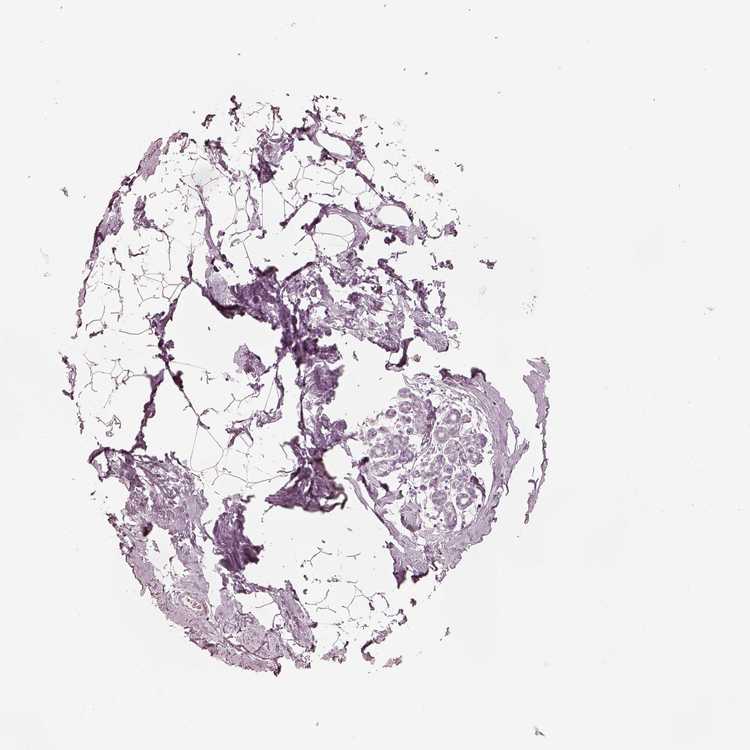

BREAST - HPA RNA-seqi

The RNA-seq details section shows detailed information about the individual samples used for the transcript profiling and results of the RNA-seq analysis.

Information about each individual sample is listed below, including gender, age, a tissue section image and estimated fractions of cell types. nTPM (normalized transcripts per million) values give a quantification of the gene abundance which is comparable between different genes and samples.

overview

Female, age 80

Breast sample 390

nTPM: 0

Cell types%

Glandular cells:

5

Adipocytes:

15

Other cell types:

80